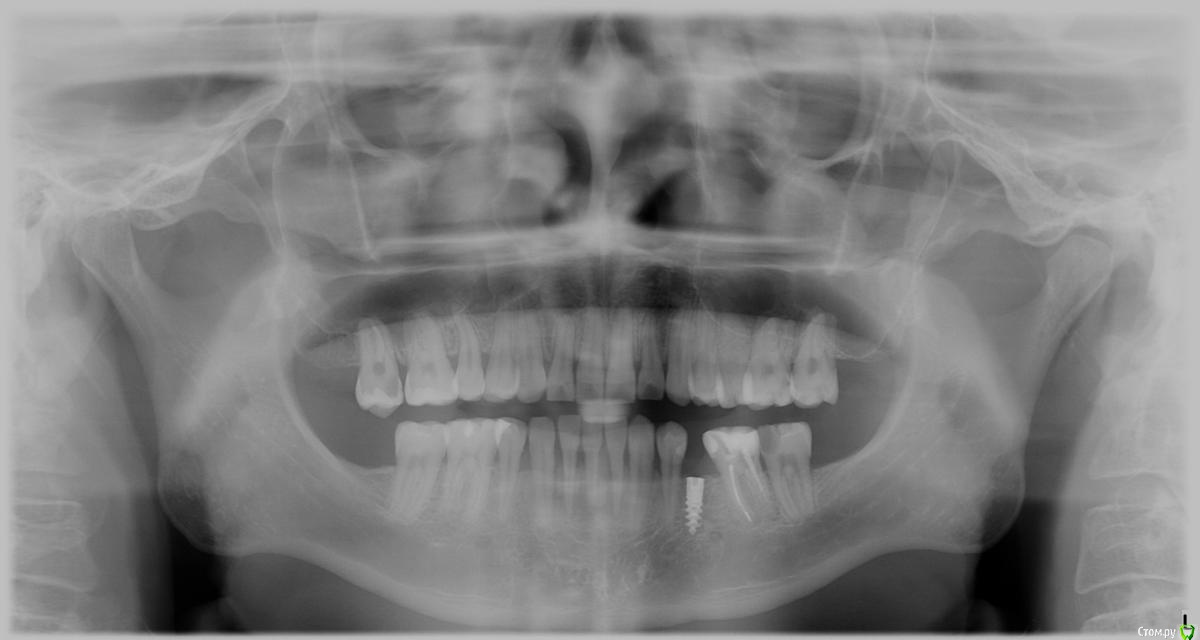

hisurfer Опубликовано 7 октября, 2015 Поделиться Опубликовано 7 октября, 2015 Добрый день!В конец марта этого года мне установили имплант roott , через месяц начался переимплантит, пришлось удалить.На вопрос, почему произошло отторжение, врач ничего толком не ответил, кроме возможной аллергии на титан (или сплав импланта), предложил попробовать установить еще раз через 2 месяца, когда кость заживет.Я решил второй раз не пробовать на авось, притом что причина первой неудачи осталась неясна. Сейчас интересует вопрос, возможно ли по снимкам определить, почему произошло отторжение?Также нужен совет по дальнейшему лечению. Хочу еще раз попробовать установить имплант.Уже консультировался, но хотелось бы услышать еще мнения, ибо страшно. Приложил снимок сразу после установки импланта (1) и перед удалением (2), и скрины кт недельной давности.При необходимости могу выложить полный КТ. Благодарю! 2_20150423 14-28-17.bmp Ссылка на комментарий